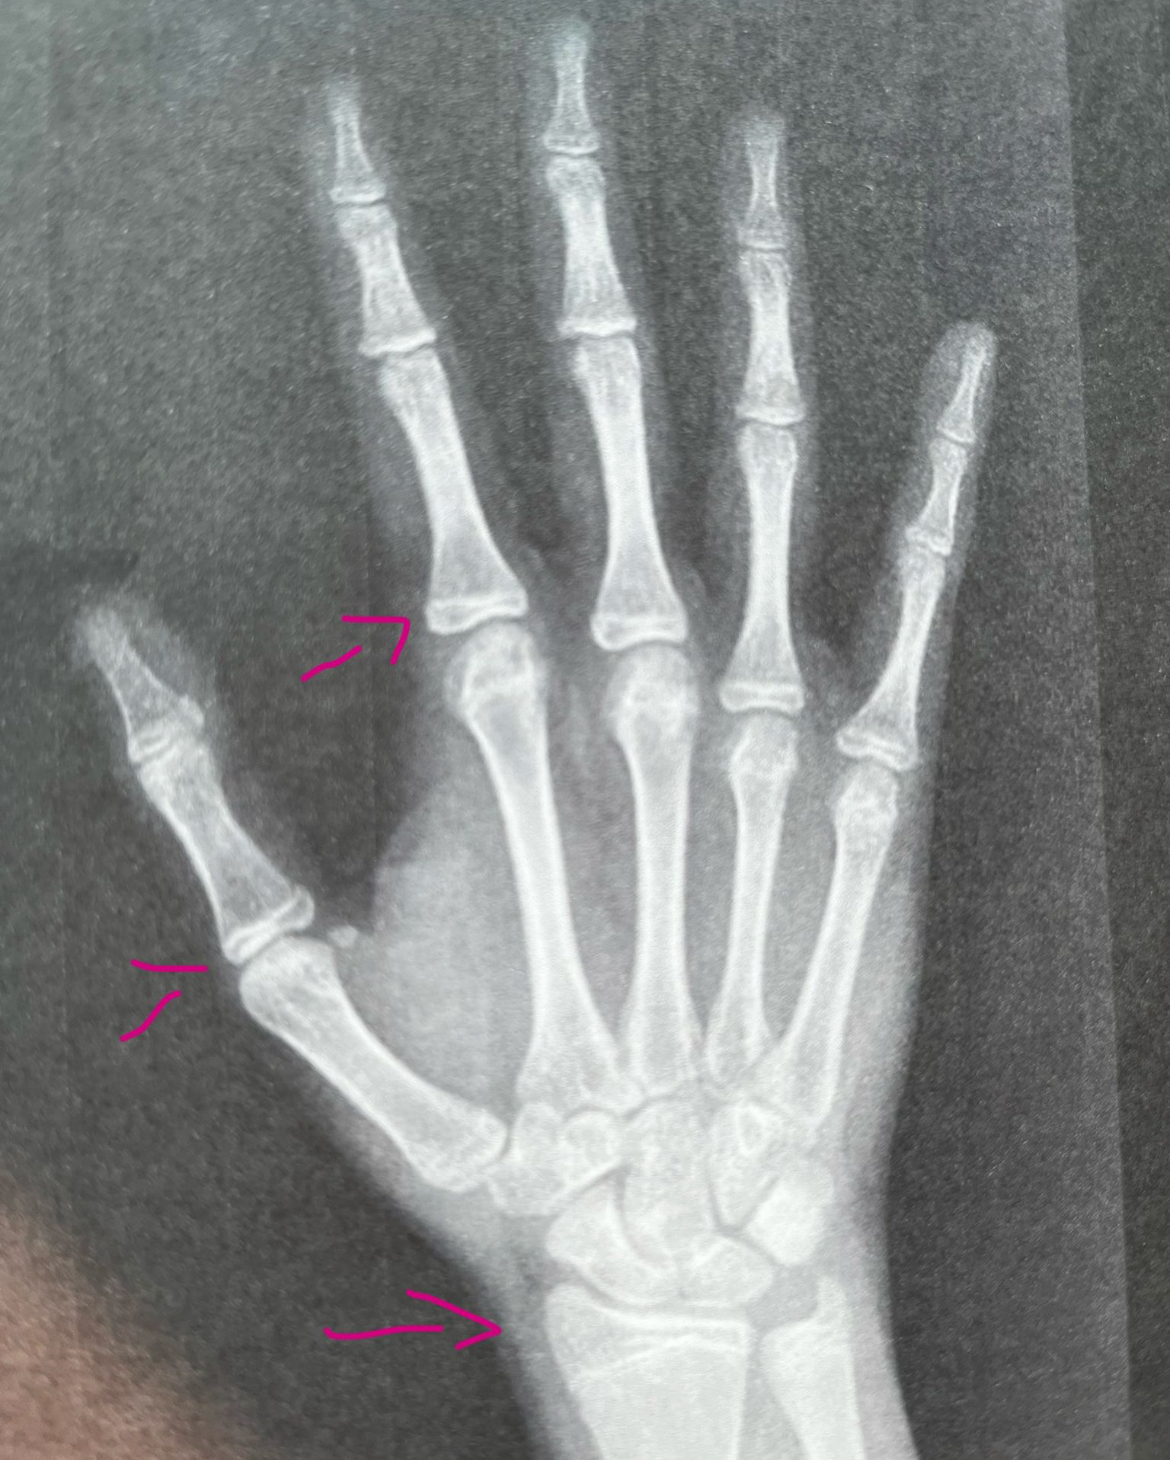

This is my wrist x-ray i did 3 weeks ago

This is my wrist x-ray i did 3 weeks ago